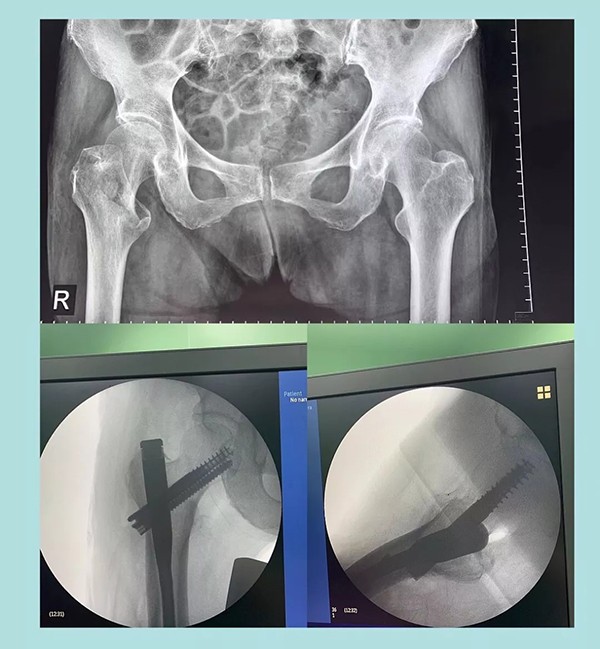

幾天前,蒲奶奶不小心摔了一跤倒地不起,到家附近醫(yī)院檢查后被診斷為右側(cè)股骨粗隆粉碎性骨折。醫(yī)生告知家屬,這種骨折對(duì)于老人來(lái)說(shuō)非常棘手,建議保守治療。為提高老人生活質(zhì)量,家人商量后決定放手一搏,在打聽(tīng)到我院關(guān)節(jié)科對(duì)這種病例治療效果非常理想后,立即轉(zhuǎn)往我院。

經(jīng)過(guò)內(nèi)科疾病的治療調(diào)理,總體符合手術(shù)條件后,羅軍主任帶領(lǐng)手術(shù)團(tuán)隊(duì)為老人實(shí)施了閉合復(fù)位Intertan髓內(nèi)釘微創(chuàng)手術(shù)。為避免全麻對(duì)肺功能的影響,術(shù)中沒(méi)有使用常規(guī)的全麻氣管插管,而是采取神經(jīng)阻滯麻醉。術(shù)前老人嚴(yán)重貧血,為盡可能減少術(shù)中出血,手術(shù)采用微創(chuàng),且在半個(gè)小時(shí)內(nèi)順利完成。術(shù)后老人沒(méi)有明顯疼痛,術(shù)后一周即下地行走。